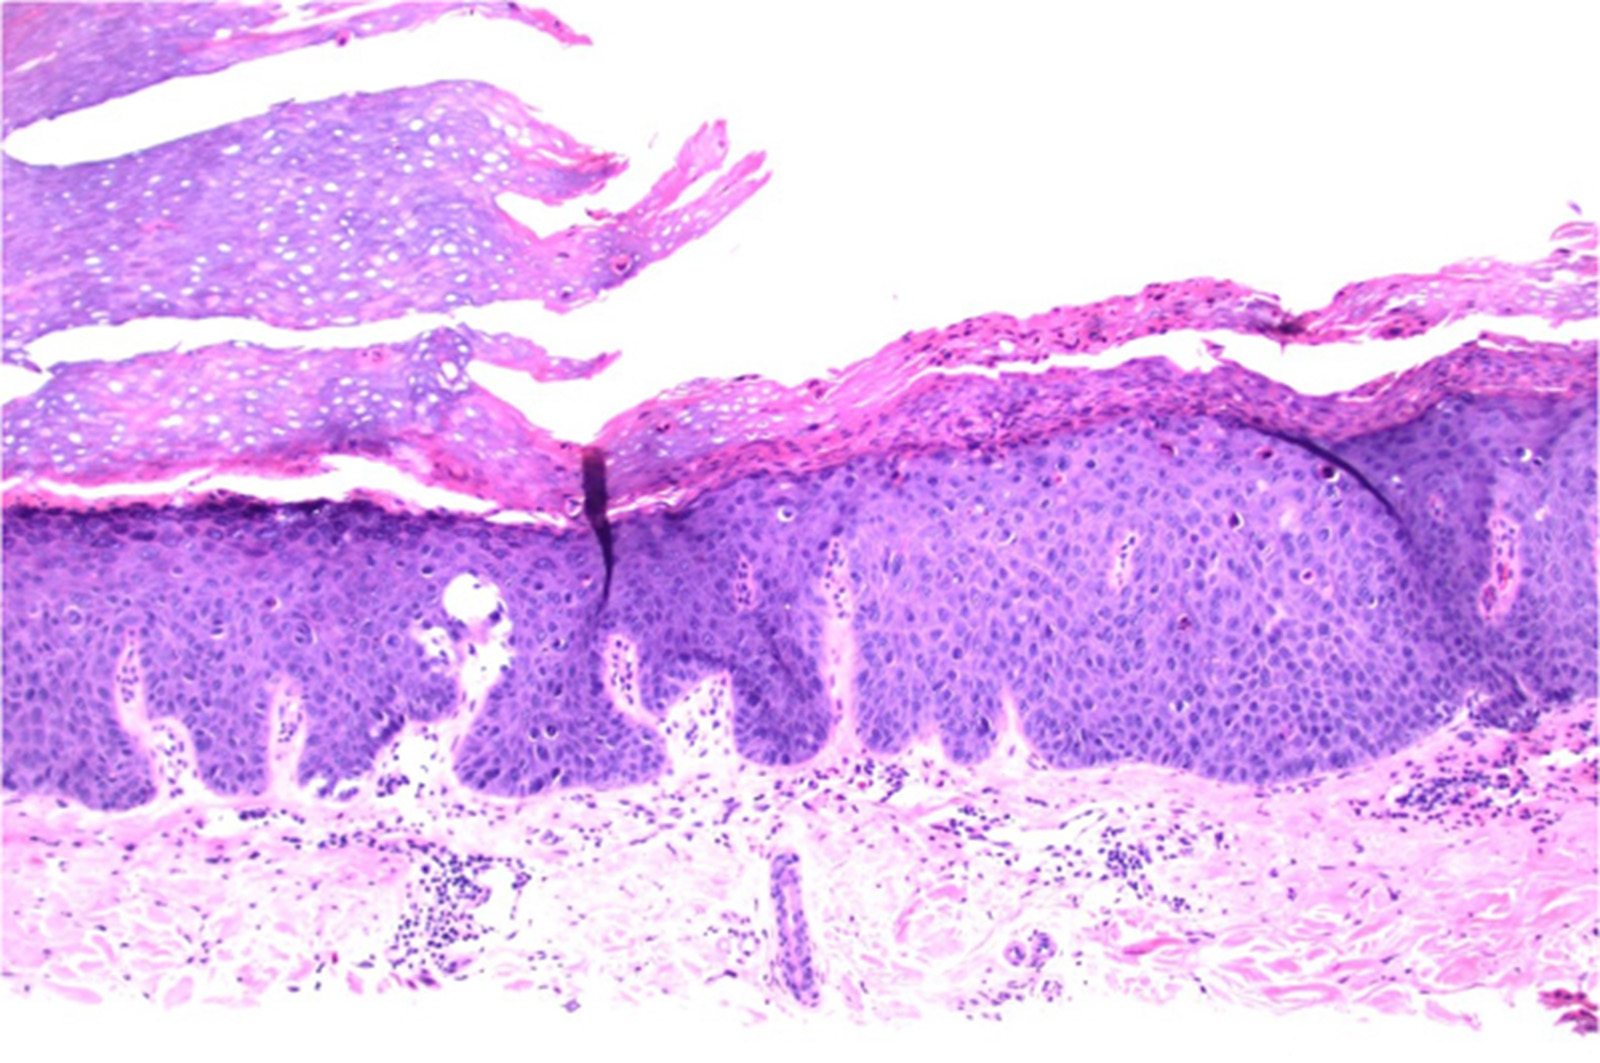

Image for DWII of microscopy of hypokeratosis

Image from reference 10.

Results: All patients were middle aged or elderly. [Although pediatric cases are unusual, congenital cases have been reported (3,4)] Nine patients were women and one was a man. The lesions showed predilection for the skin of the thenar and hypothenar regions of the palm or the medial side of the sole.[Rarely, lesions have been reported on nonacral sites, such as the chest. (5)] Histopathologic study demonstrated a depression of the epidermis, with a sharp stair between normal and involved skin. The epidermis covering the depression showed markedly thinner horny layer and a slightly diminished granular cell layer when compared with adjacent noninvolved skin. Keratinocytes of the squamous cell layer, granular cells, and corneocytes showed, otherwise, a normal appearance. Serial sections failed to demonstrate cornoid lamellation.